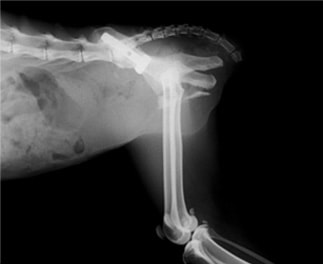

術後レントゲン写真